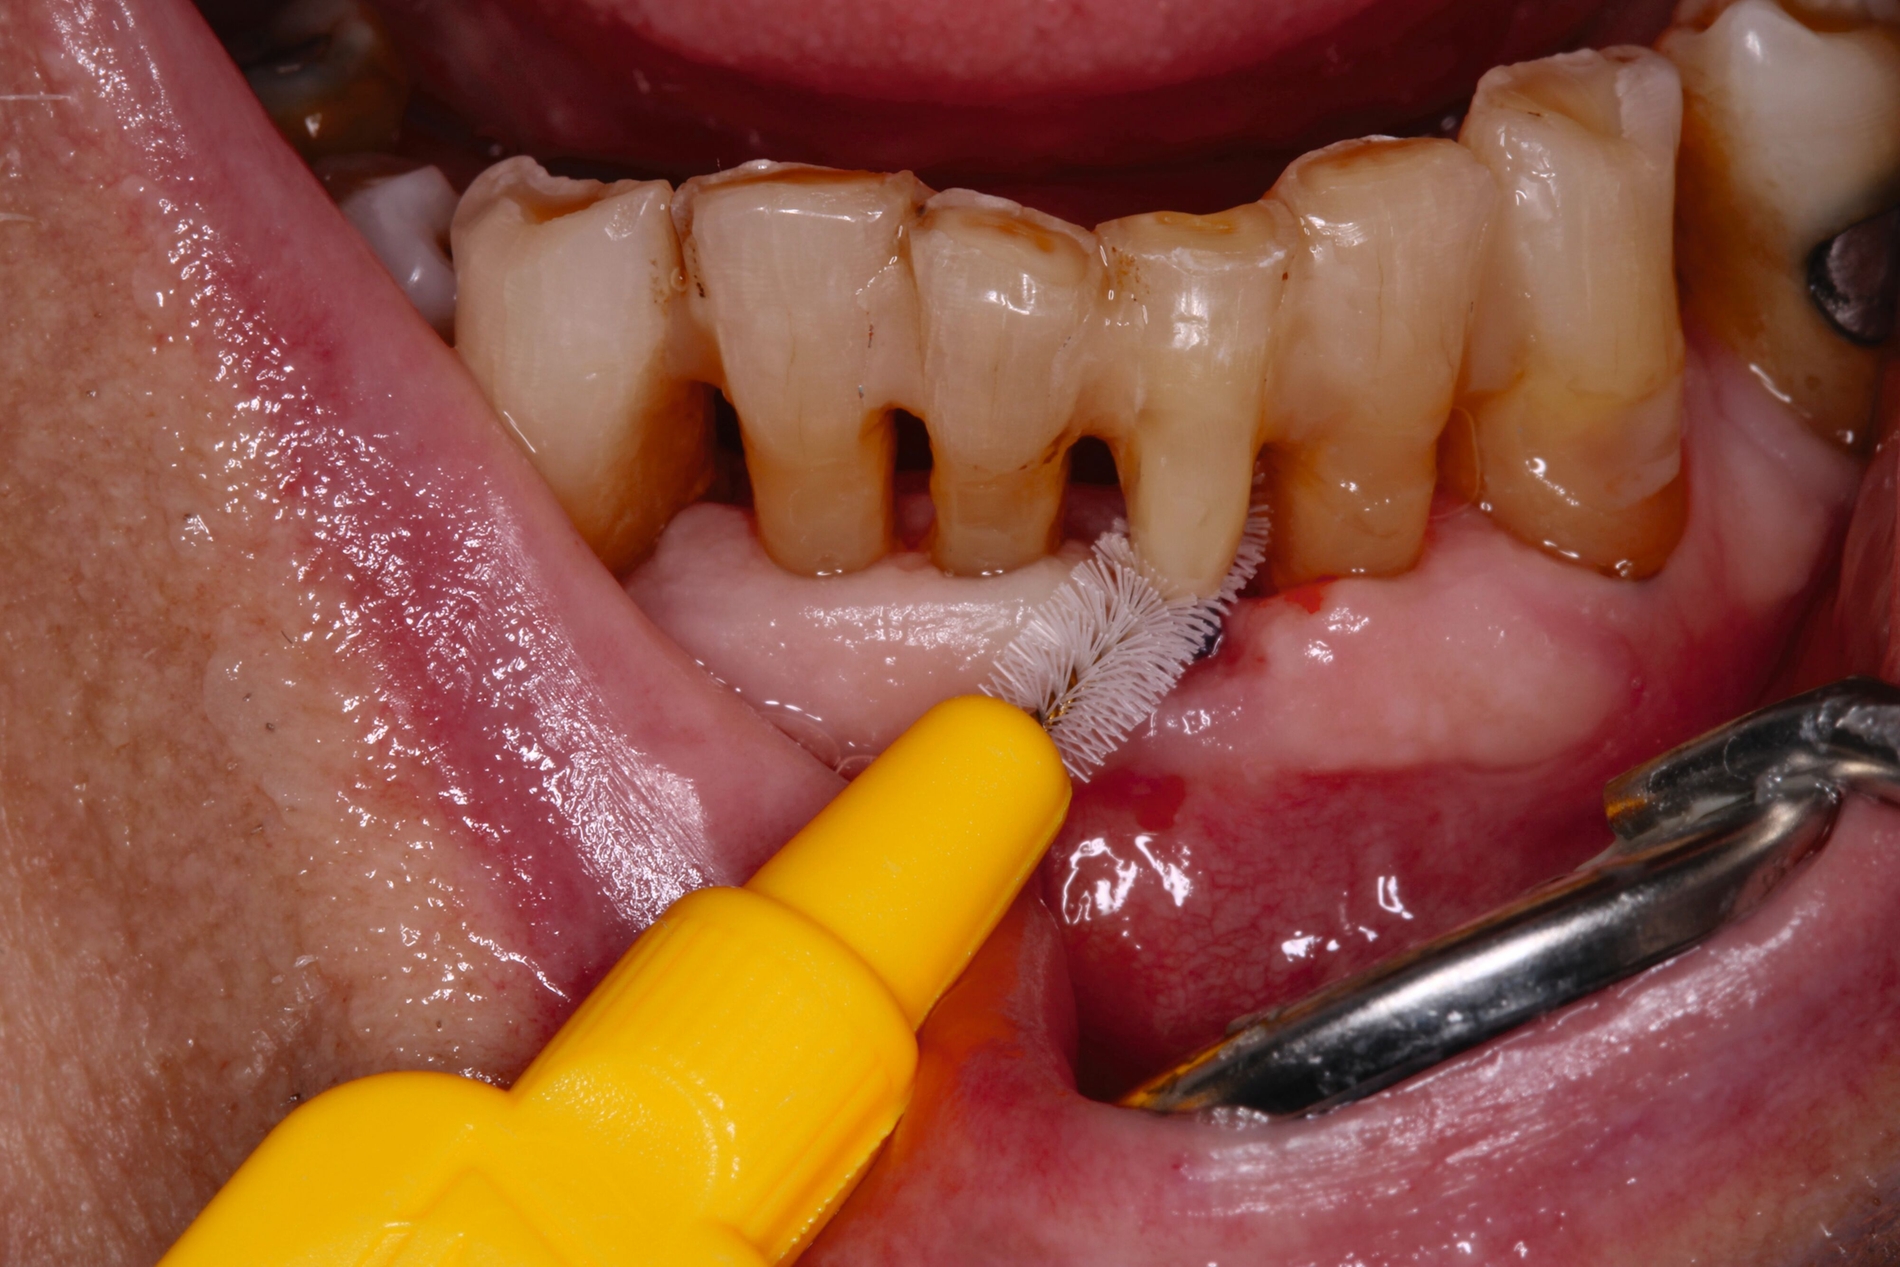

Auch aufseiten der Pflege wurden durch die Einführung des DNQP-Expertenstandards Rahmenbedingungen zur Verbesserung der Mundgesundheit bei Personen mit Pflegebedarf geschaffen. Der Expertenstandard definiert unter anderem das Aufgabenspektrum, den Verantwortungsbereich und das nötige Kompetenzprofil von Pflegefachpersonen in Bezug auf die Mundgesundheit bei Personen mit Pflegebedarf. Als zentrale Anforderung an Pflegefachpersonen formuliert der Expertenstandard zudem die Kompetenz, einschätzen zu können, wann weitere zahnmedizinische Expertise hinzuzuziehen ist [Sirsch et al., 2022]. Um die Maßnahmen zur Förderung der Mundgesundheit nachhaltig zu implementieren, ist ein dauerhafter Austausch zwischen Zahnmedizinern und Pflegeverantwortlichen, unter regelmäßiger Einbeziehung geriatrisch-hausärztlicher Expertise notwendig. Die Telemedizin verspricht in Bezug auf die Verbesserung des Zugangs zu zahnmedizinischen Leistungen für Personen in Pflegeeinrichtungen Zukunftspotenzial [Aquilanti et al., 2020]. Nicht in allen Fällen sind Defizite der Mundhygienefähigkeit absehbar. Nach Unfällen oder Schlaganfällen sind Patientinnen und Patienten eventuell von einem auf den anderen Tag nicht mehr in der Lage, ihre Mundhygiene selbstständig adäquat durchzuführen (Abbildung 4).

Patientinnen und Patienten mit stark reduzierter Therapiefähigkeit profitieren in besonderem Maß von zeiteffektiven Methoden und Materialien, zum Beispiel Bulk-fill-Kompositen, Reparaturfüllungen, Glasionomerzementen oder Intraoralscans. Die Therapiefähigkeit kann – ähnlich wie in der Kinderzahnmedizin – durch ein vertrauensvolles Verhältnis optimiert werden. Anders als in der Kinderzahnmedizin gibt es in der Alterszahnmedizin aber keine altersassoziierten Kontraindikationen für zahnmedizinische Interventionen. Voraussagbare Therapieergebnisse sind von besonderer Bedeutung, um erneute Behandlungen zu vermeiden. Das gesamte Spektrum zahnmedizinischer Interventionen kann bei der Behandlung von Personen mit Pflegebedarf sinnvoll sein. Die Abbildungen 6 bis 9 zeigen zahnmedizinische Interventionen bei Personen mit ausgeprägter Frailty (Stufe 7 der klinischen Frailty-Skala).